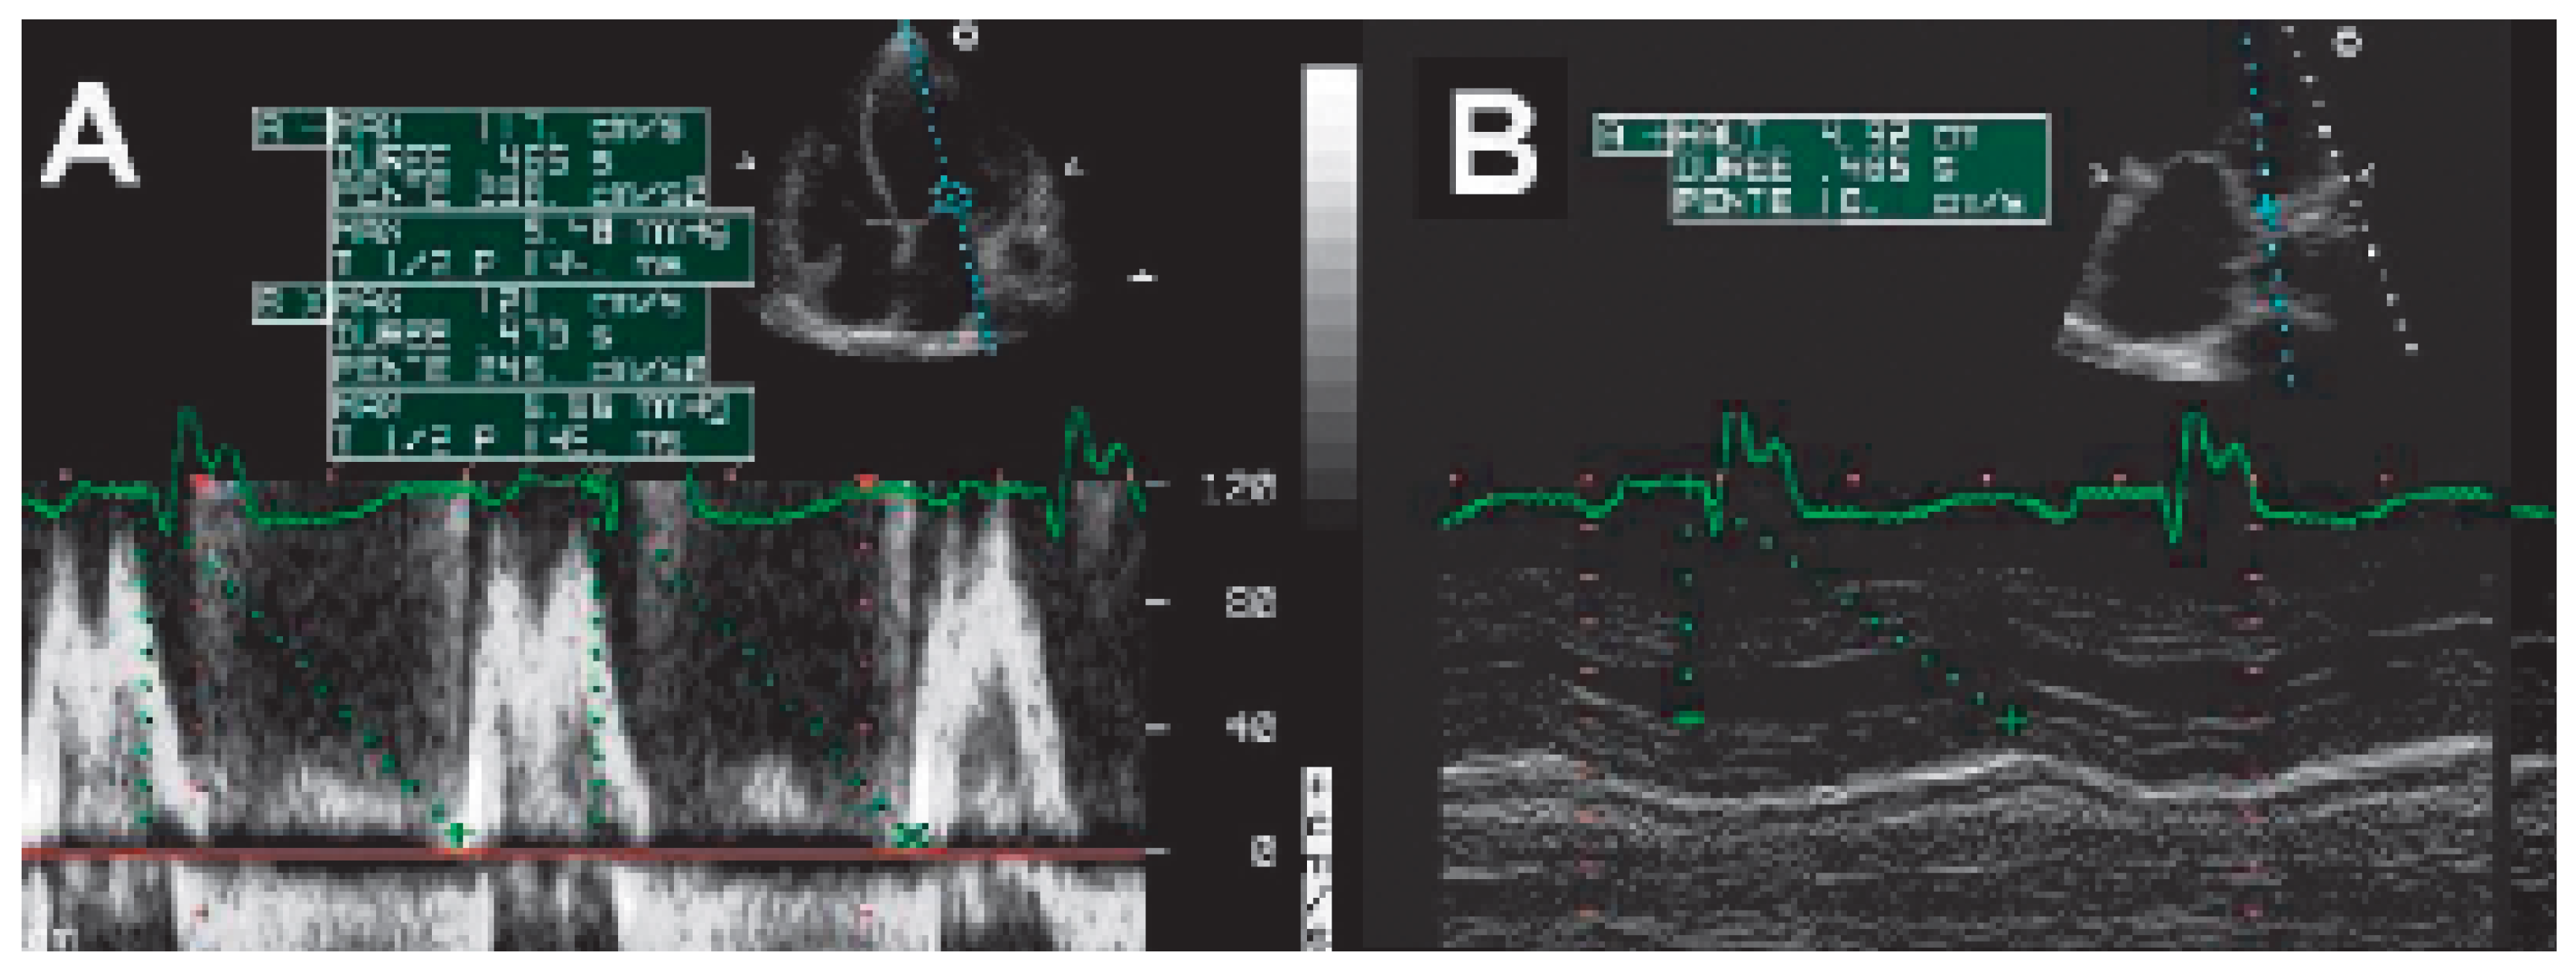

AV interval optimisation

The Ritter method (Figure 6)

The iterative method

The aortic velocity-time integral (VTI) method